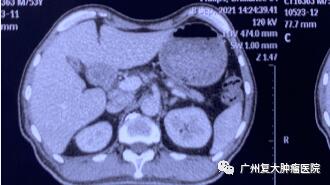

影像圖片顯示

圖2

為求進(jìn)一步診療,2020年11月,患者來(lái)廣州復(fù)大腫瘤醫(yī)院就診。入院完善相關(guān)檢查發(fā)現(xiàn):CA-199指標(biāo)高達(dá)2289u/ml(CA-199屬胃腸道腫瘤相關(guān)抗原,是一種腫瘤標(biāo)志物,正常值≤37u/ml);肝實(shí)質(zhì)內(nèi)有多個(gè)結(jié)節(jié)狀,較大者約4.3×3.8cm。胰腺體、尾部均有腫塊,并鄰近腸管、脾靜脈局部粘連不清,大小約4.3x3.3cm。